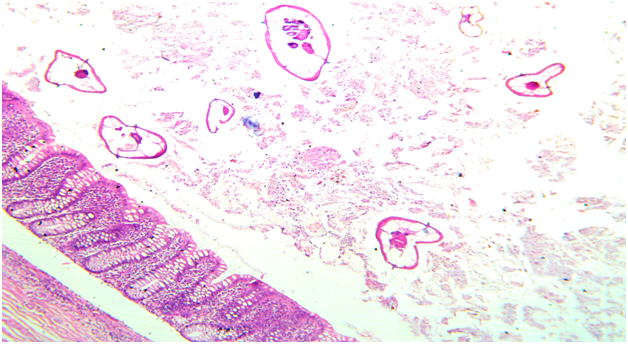

A 22 year old male patient came to the casualty department with pain in abdomen. On physical examination there was right iliac fossa tenderness. A laboratory investigation revealed a normal Complete Blood Count (CBC). Serum immunoglobulins levels were not done in this patient as clinicians did not suspect parasitic infection as a cause of acute appendicitis.Ultrasonography was performed and did not show inflammation of appendix or any other abdominal organ. Clinical diagnosis of acute appendicitis with unkown etiology was made and patient underwent open appendicectomy. The specimen was sent for histopathological examination to know the exact cause of appendicitis. On gross examination appendix appeared normal with presence of fecolith. Microscopic examination revealed mucosa with inflammatory infiltrate predominantly comprising of eosinophils which is most commonly seen in parasitic infection and lumen showed parasite of Enterobius Vermicularis (Figure 1&2). The rest of the layer submucosa, muscle layer and serosa appeared normal and showed no evidence of neutrophilic infiltrate or congested blood vessels which is usually is seen in acute appendicitis without parasitic infection. (Figure 3). The diagnosis of acute appendicitis secondary to Enterobius Vermicularis infection was given. Post operatively a dose of mebendazole 100mg was given and patient is being followed up.

Figure 1 Microscopic photo showing mucosa of appendix with lumen showing multiple enterobious vermicularis parasite. (HE, X10)